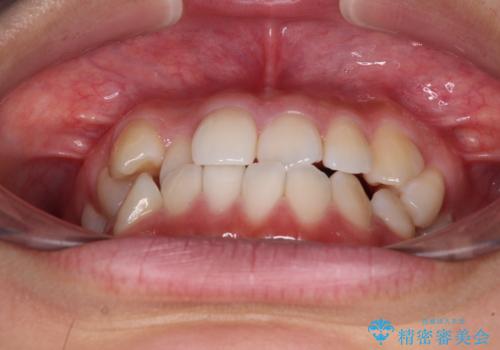

- 前歯のデコボコを治したいとのことで来院された患者様です。

インビザラインによるマウスピース矯正も適用となる歯列でしたが、できる限り楽して、短期間で治したいとのことで、ワイヤー装置にて矯正治療を行うこととしました。